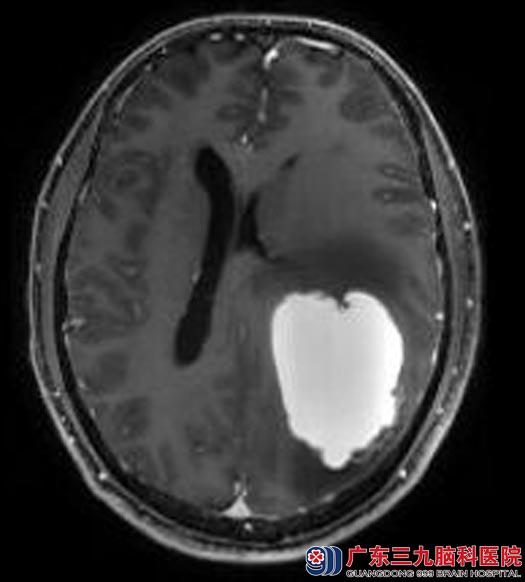

为进一步了解病情,林先生来到广东三九脑科医院,MR检查提示:左侧颞顶叶示类圆形病灶,大小约5.3cm×4.0cm×5.5cm,可疑肿瘤卒中。